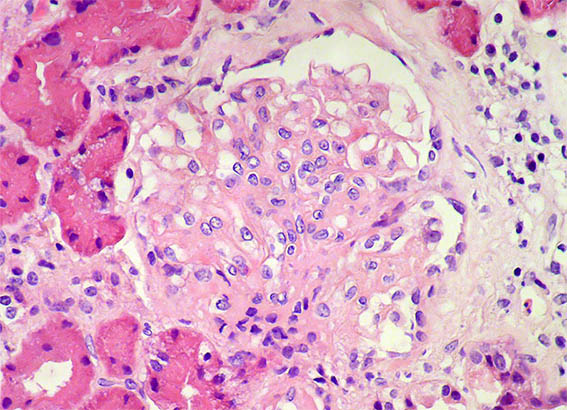

Figura 3.

H&E, X400. Lesión esclerosante segmentaria.